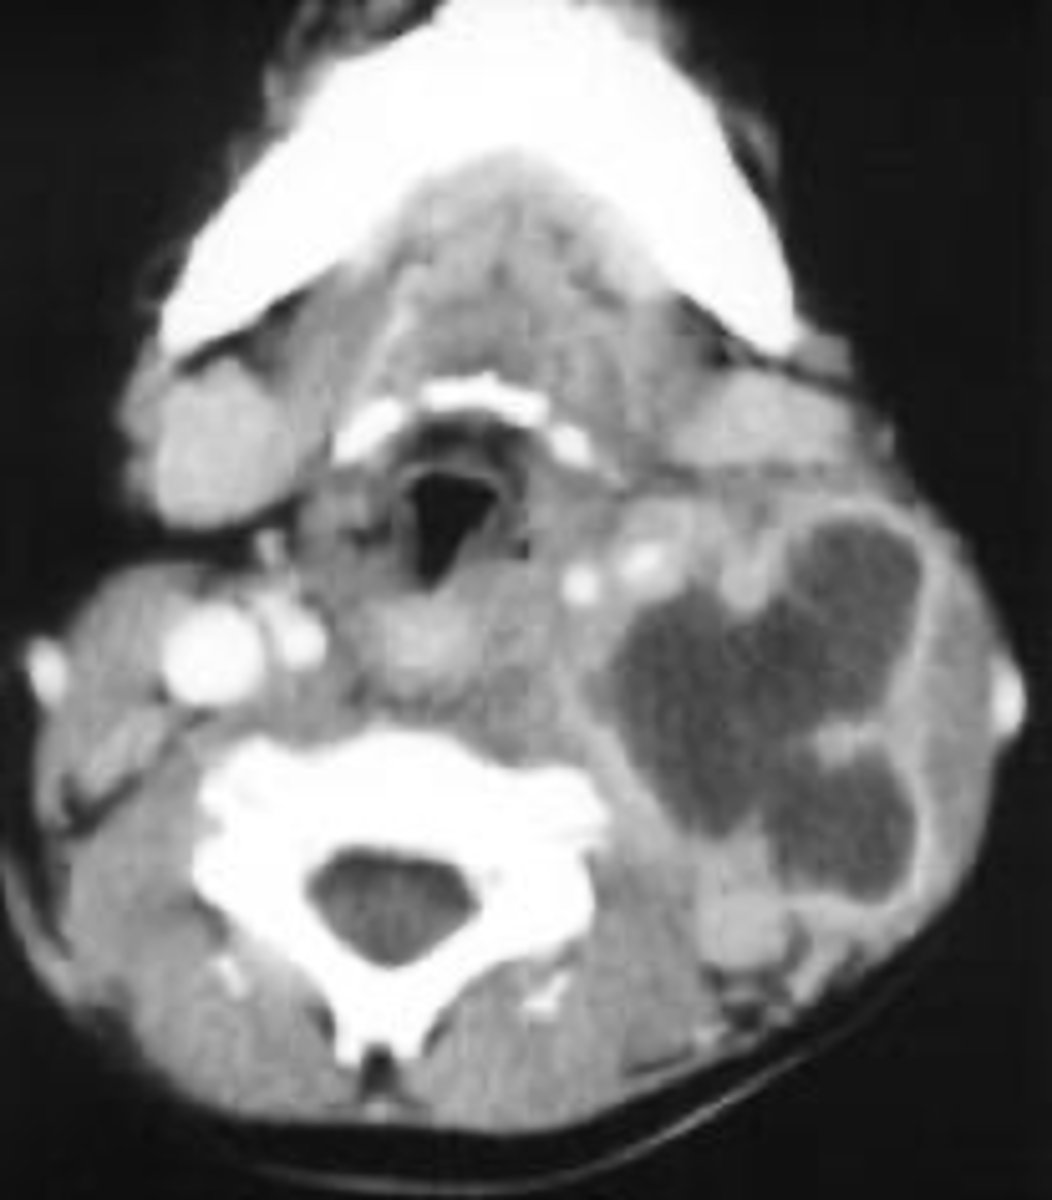

CT

ID the type of Imaging modality:

- Pano

- CT

- CBCT

- MRI

- Technetium 99 bone scans

- PET